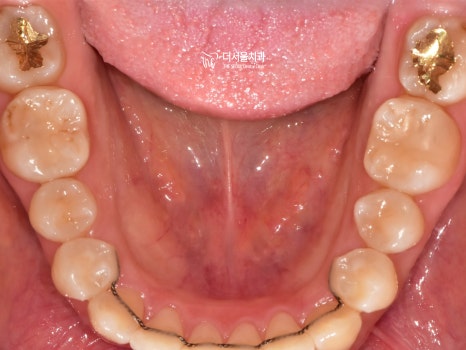

교합면에서 봤을 때에, 치열이

알파벳 U 자 처럼 보여지죠?

윗니와 아랫니가 잘 맞물리게끔 재 배열을 했습니다.

즉, 기능성도 같이 향상 되었다는 뜻입니다.